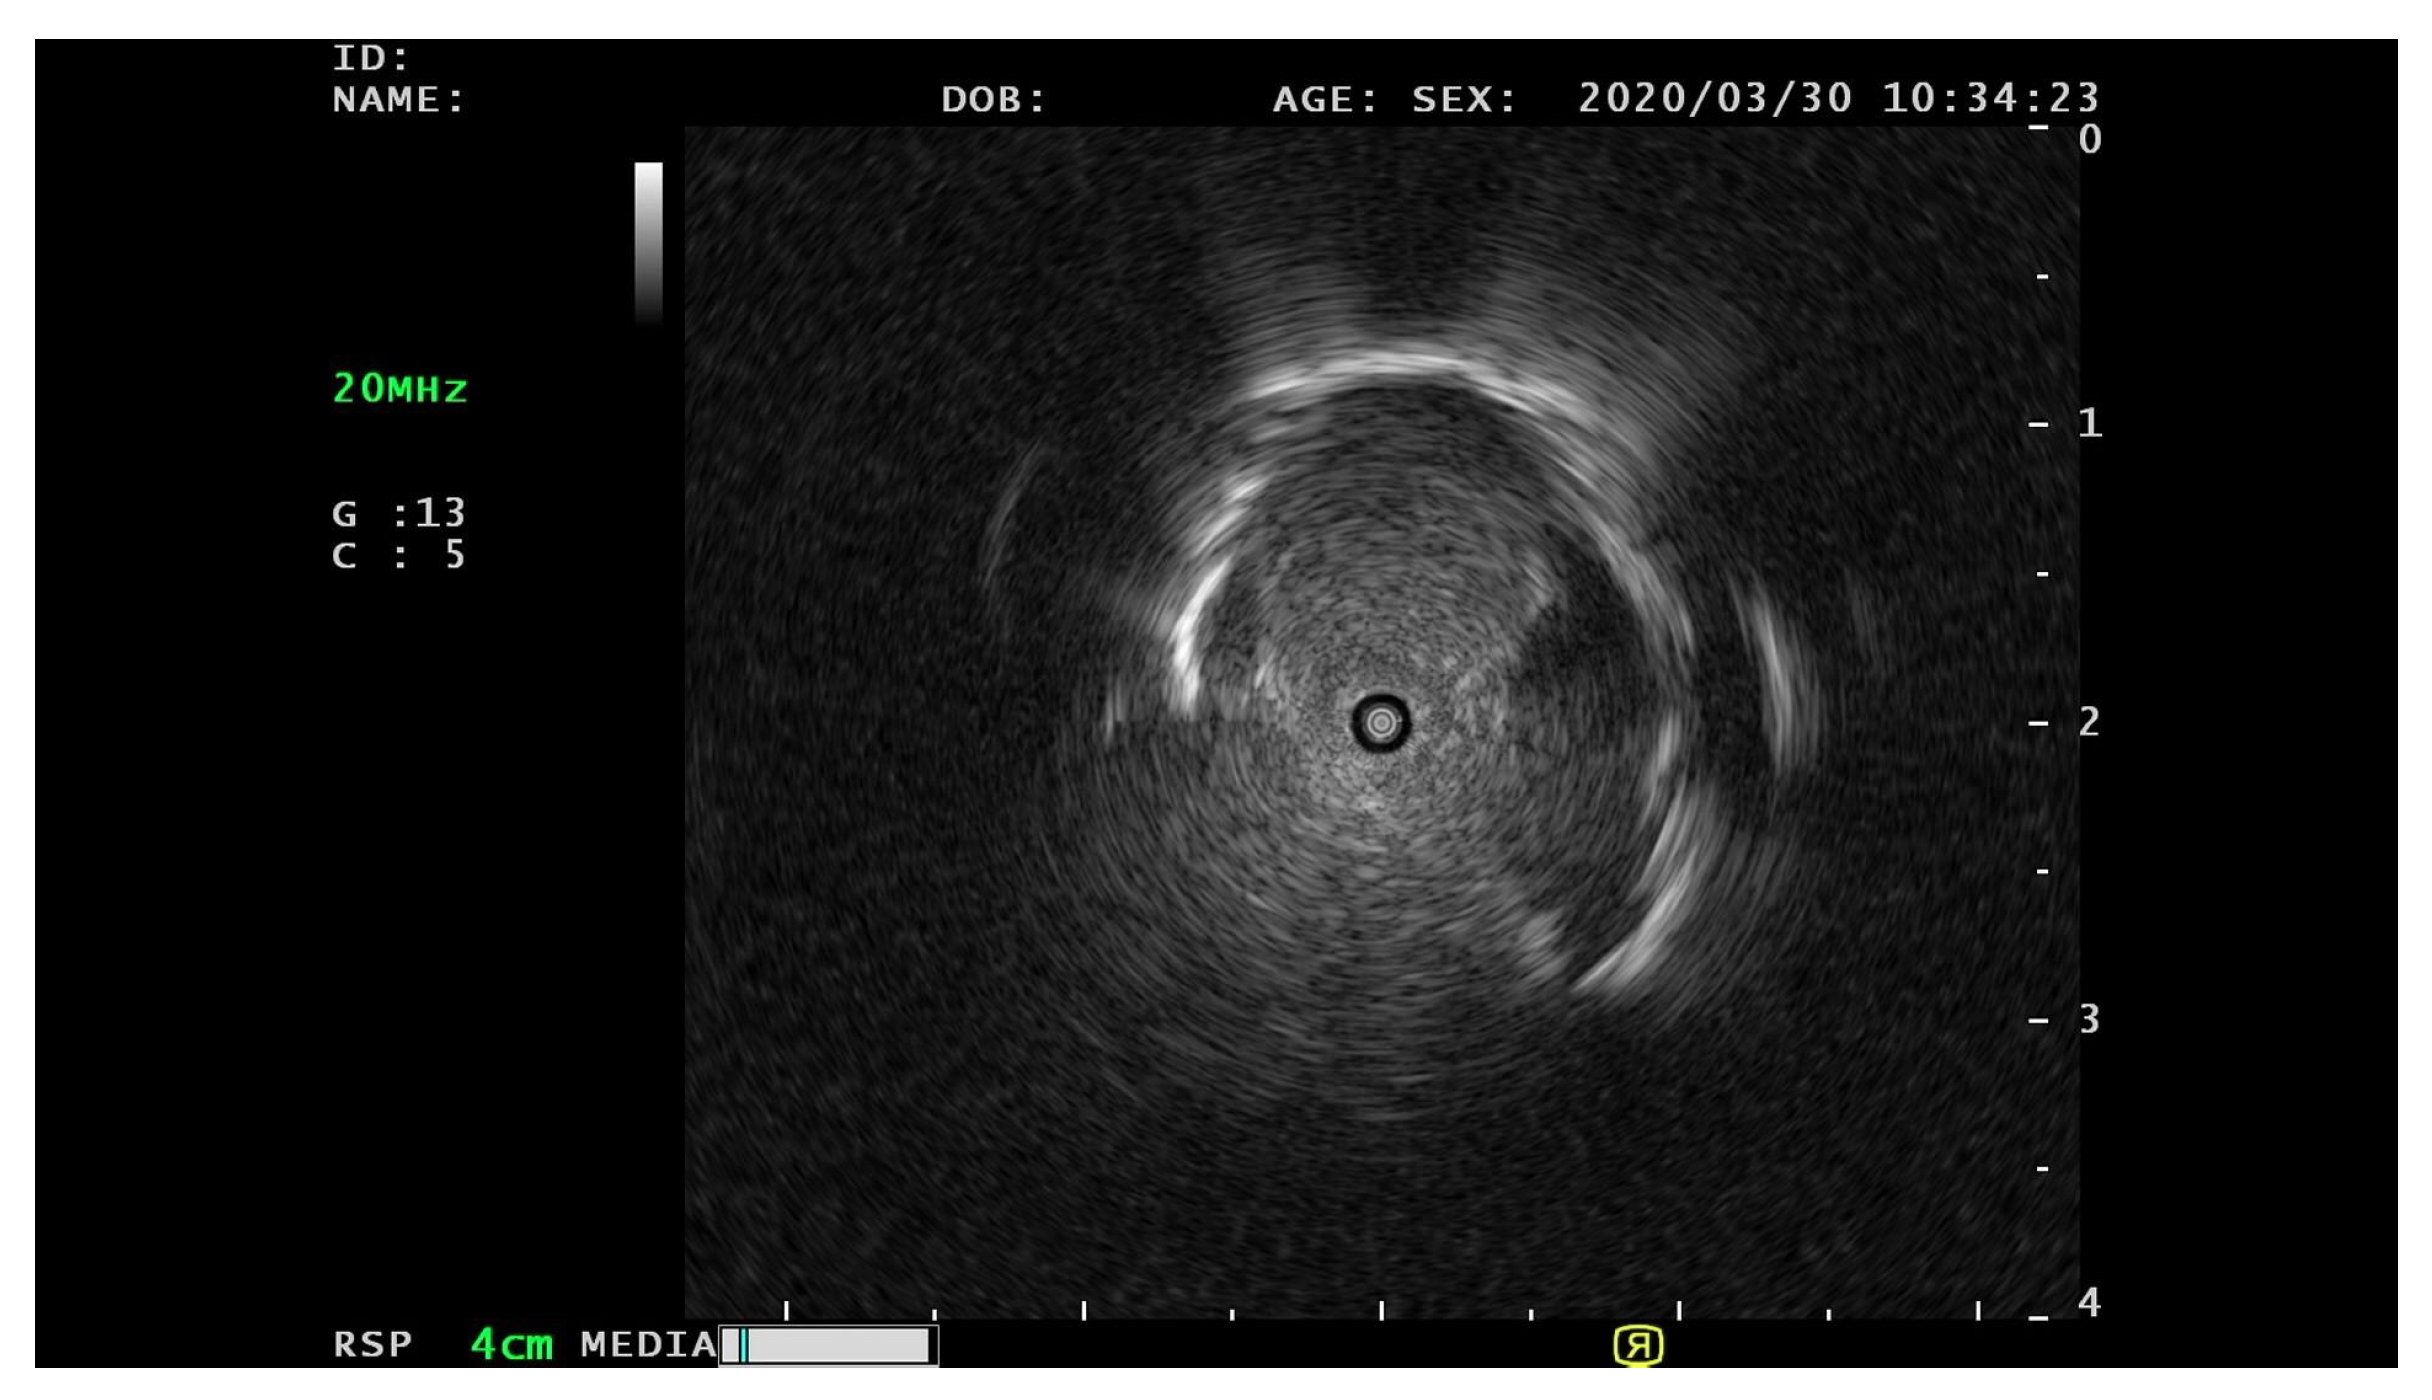

2. Experimental Materials

3.1. Data Pre-Processing